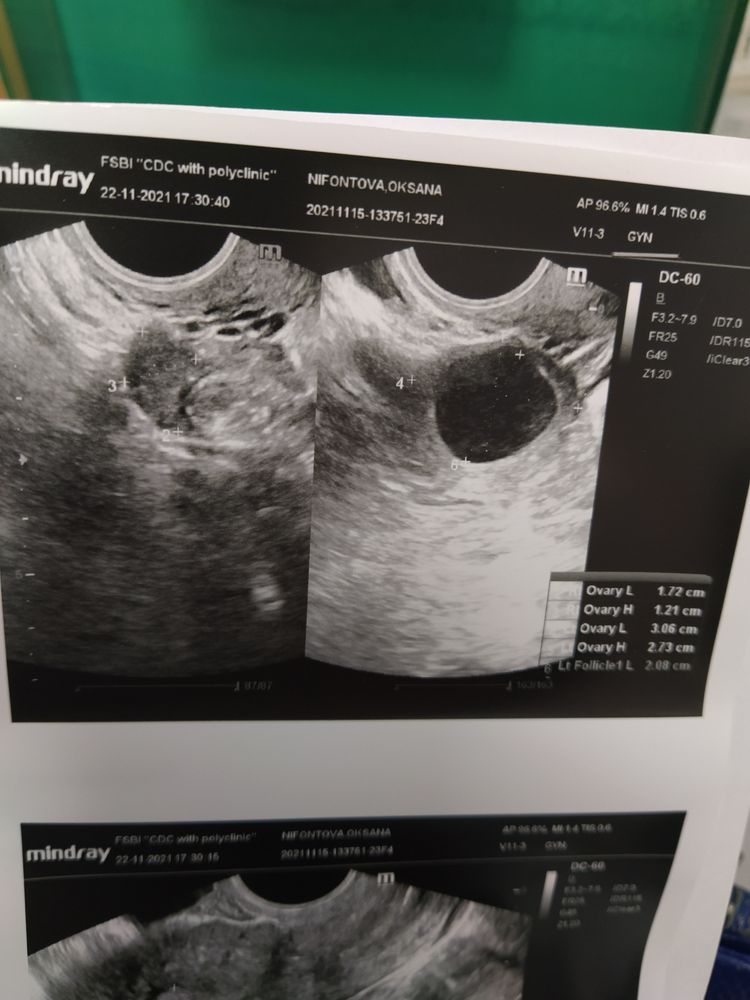

Это фолликул или ЖТ?

Сурмама Софа, почему киста то? Фолликул ломает 21-22 мм.

20,8мм это ещё не киста, доминантный фолликул на фото, лопнет в ближайшее время, делали ещё тесты на о?

Это фолликул.

Это фоллик.